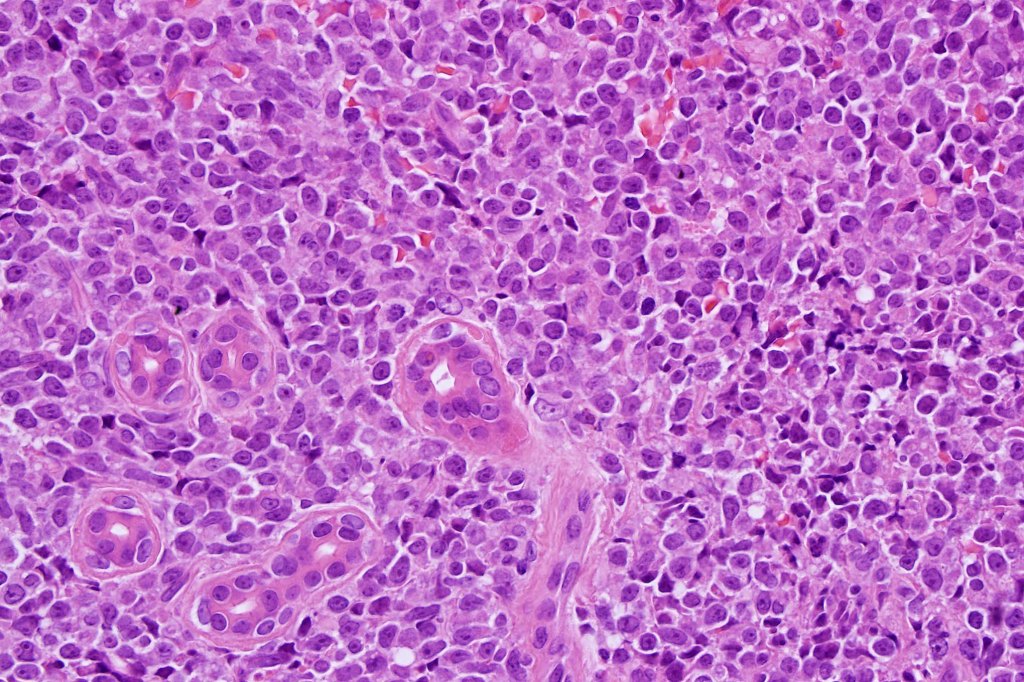

Histological features

. Monotonous blast cells with gray-blue cytoplasm & irrregular vesicular nuclei with prominent nucleoli

AML & chronic myeloid leukemia can be distinguished by the presence of myeloid markers although distinction can sometimes be very difficult. If too much attention is given to the plasmacytoid morphology, a plamsa cell tumor may be readily excluded with IHC.